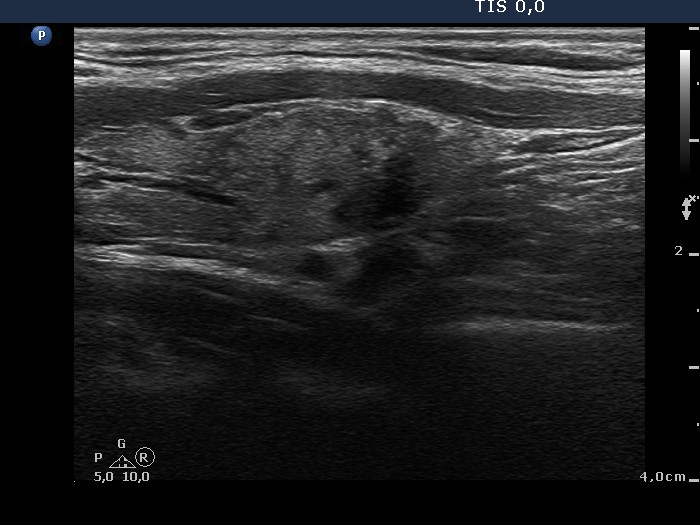

100 consecutive cases of papillary cancer - case 039 (ultrasonographic picture 6)

Left lobe, another longitudinal view.